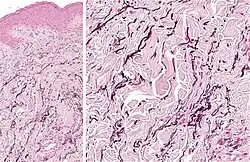

Elastosis is the buildup of elastin in tissues, and is a form of degenerative disease. There are a multitude of causes, but the most commons cause is actinic elastosis of the skin, also known as solar elastosis, which is caused by prolonged and excessive sun exposure, a process known as photoaging. Uncommon causes of skin elastosis include elastosis perforans serpiginosa, perforating calcific elastosis and linear focal elastosis.[12]

| Actinic elastosis (most common, also called solar elastosis) |

Elastin replacing collagen fibers of the papillary dermis and reticular dermis |

| Elastosis perforans serpiginosa | Degenerated elastic fibers and transepidermal perforating canals (arrow in image points at one of them)[13] |

| Perforating calcific elastosis | Clumping of short elastic fibers in the dermis.[13] |

| Linear focal elastosis | Accumulation of fragmented elastotic material within the papillary dermis and transcutaneous elimination of elastotic fibers.[13] |